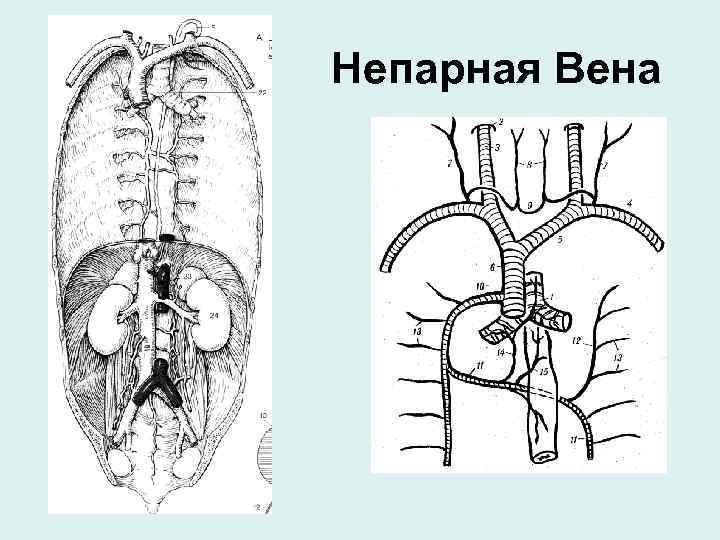

Непарная Вена • истоки: правая восходящая поясничная вена • Притоки: задние межреберные вены, вены позвоночных сплетений, пищеводные, бронхиальные, перикардиальные, медиастинальные, полунепарная вена

Непарная Вена

Непарная Вена